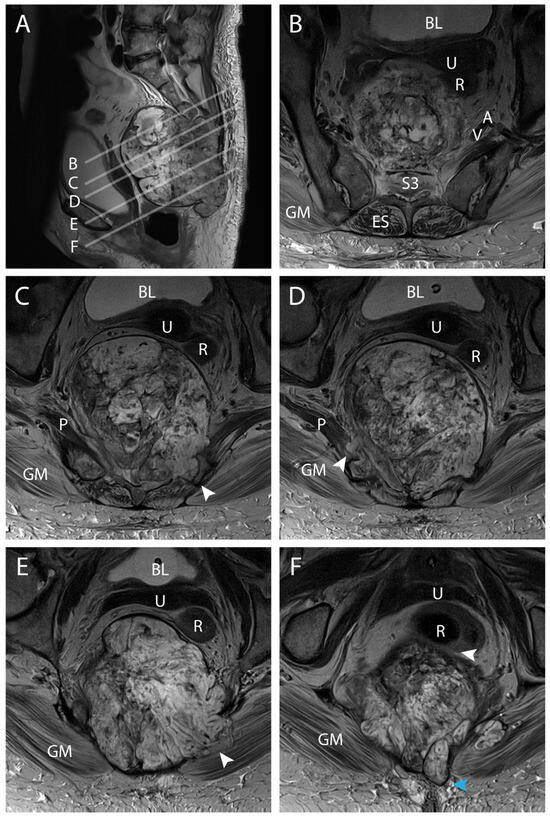

4.3. Surgical Technique